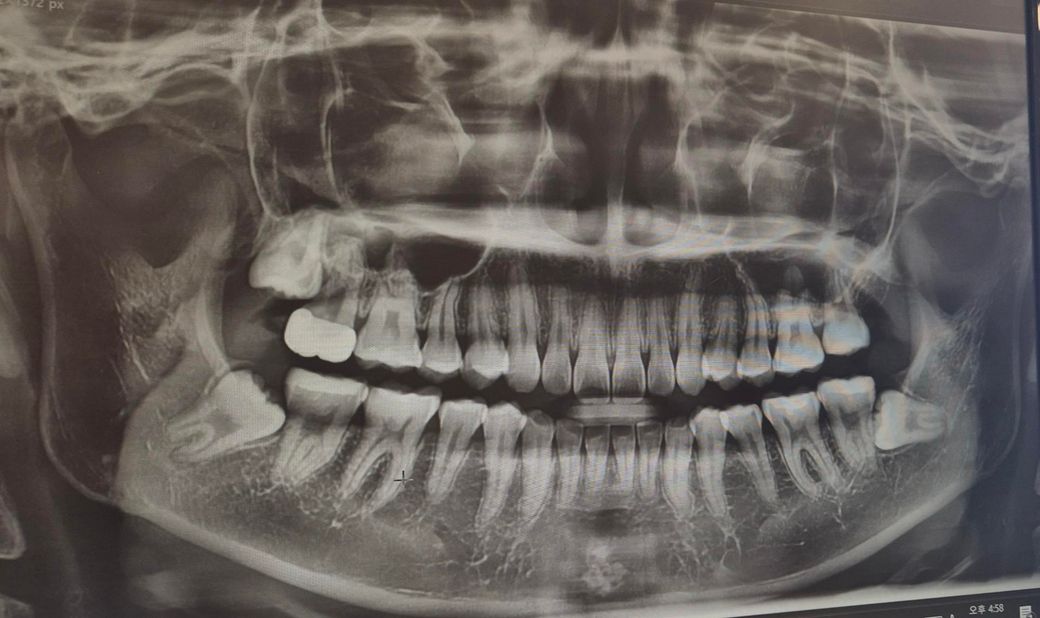

사진상으로 왼쪽 아래 맨끝 어금니입니다.

밥 먹을때나 양치할 때는 괜찮다가 손으로 어금니 윗부분을 문지르거나 살짝 흔들면? 좀 시린 느낌이 나요. 최근에 갔을 때는 육안으로 봤을 때도 엑스레이 상으로도 문제없다는 진단을 받았는데요. 그냥 아픈걸까요? 아니면 어금니 윗부분이 마모된걸까요

사진 상으로 명확히 보이진 않지만 증상이 지속된다면 사랑니를 먼저 발치해봐야 할 듯 합니다.

엑스레이 상으로는 사랑니떄문에 치아뒷면에 충치가 잇는거 같습니다. 일단 사랑니 발치후에 다시 치아를 확인해보시는게 좋을것같습니다.

치아 마모 양상이 관찰되는데요 이갈이나 이 악물기로 인한 치아 마모, 손상 가능성도 있습니다

육안상이나 사진상으로 문제가 없음에도 불구하고 치아에 불편감이 생긴다면 해당치아에 너무 강한 힘이 가해지지 않는지 확인을 하는것이 좋습니다.

치아에 불필요한 힘이 가해지게 되면 치아가 예민해 지기 때문입니다. 힘으로 인해서 생기는 불편감은 치아에 가해지는 힘이 줄어들게 되면 없어질수 있습니다.